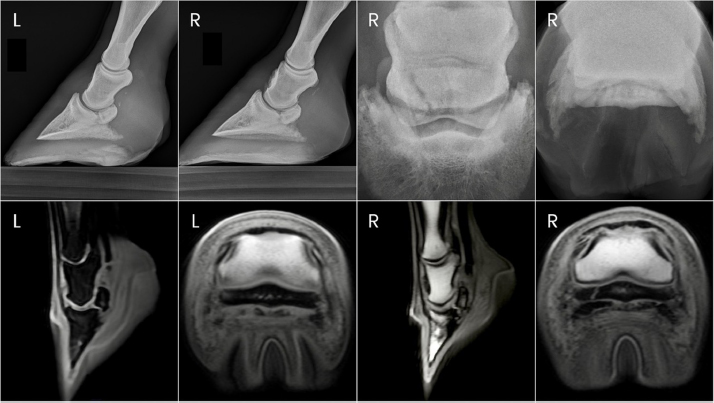

Fig. 1. Preoperative radiographs of the digits of horse 1.

Two years after donation, the gelding had progressed to displaying a grade 4/5 left forelimb lameness. This lameness was eliminated with diagnostic anesthesia of the left palmar digital nerves at the level of the proximal interphalangeal joint and replaced by a grade 4/5 right forelimb lameness. The right forelimb lameness was then eliminated with diagnostic anesthesia of the right palmar digital nerves in a similar fashion. PDN was performed as a salvage procedure to maintain pasture soundness. Abnormalities noted on the immediate preoperative radiographs included severe navicular bone degeneration bilaterally, osteoarthritis of the proximal and DIPJs bilaterally, and a focal area of mineralization in the area of the left DDF tendon just proximal to the navicular bone (Fig. 1).